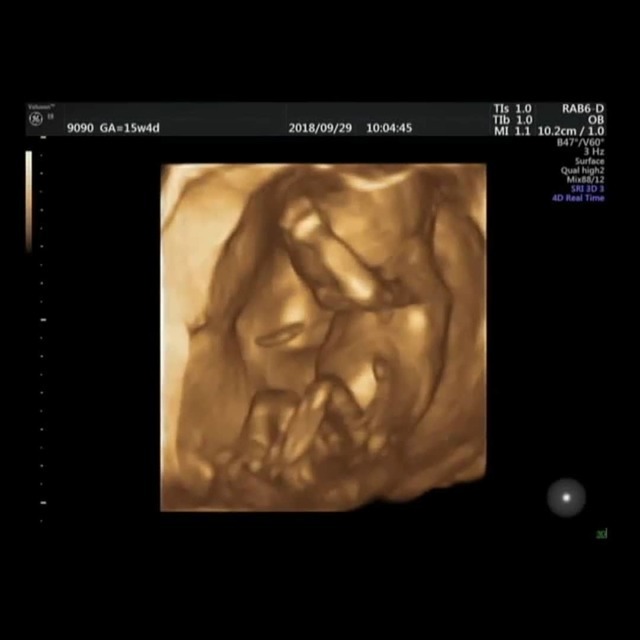

15週3日(15w3d・男の子)|kaaaa さん(25歳)

エコー写真撮影時のエピソード:

第二子にして初めて4Dエコーを貰った時のものです。まだ4ヶ月で胎動もなく今まで3Dエコーではぼんやりとした輪郭しか分からなかったのにちゃんと人の形になってる!!と感動しました。

主人も今まではエコーを見ても「ふーん」ぐらいの素っ気ない返事でしたが、これには喜んでくれました!やっぱり見やすい方が実感湧くのでしょうか。(笑)

上の子もまだ1歳でしたが、この頃から「ママのお腹には赤ちゃんがいるんだよ~~。こんなして寝んねしてるよ~~。」と話していました。毎日お腹をさすってくれて産まれる前からお姉ちゃんをしてくれています。